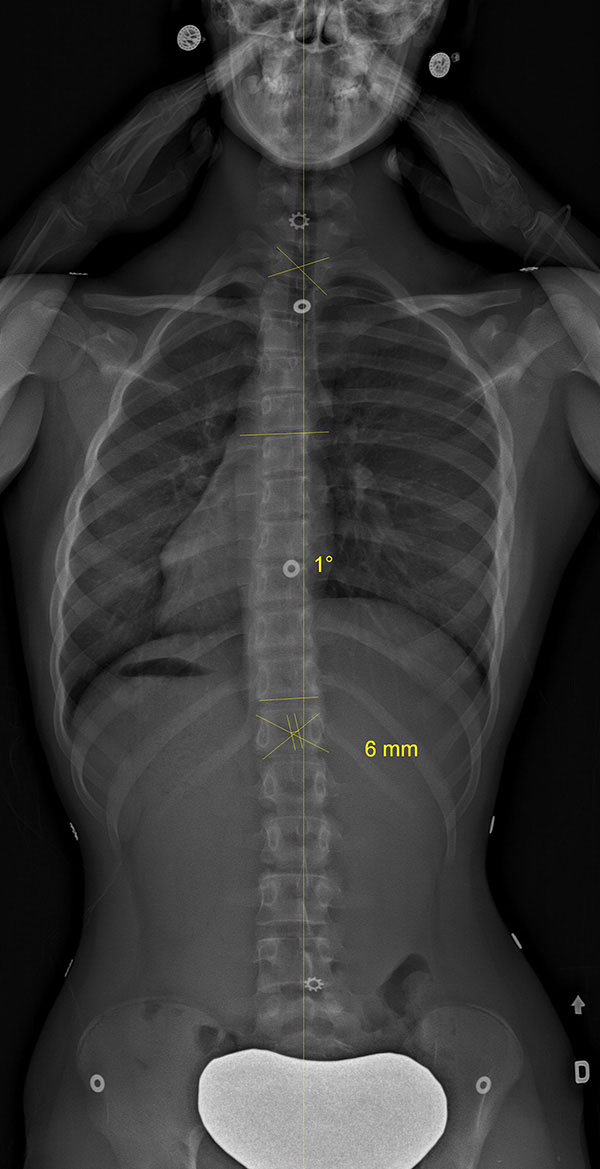

Adolescente scoliotique avant et après SpineCor®

Colonne vertébrale scoliotique d’une adolescente, avant le traitement SpineCor® et à la fin du sevrage après trois ans de port quotidien. Les radiographies démontrent une correction spectaculaire.

Colonne vertébrale de l'adolescente avant SpineCor®

Colonne vertébrale de l'adolescente avec SpineCor®